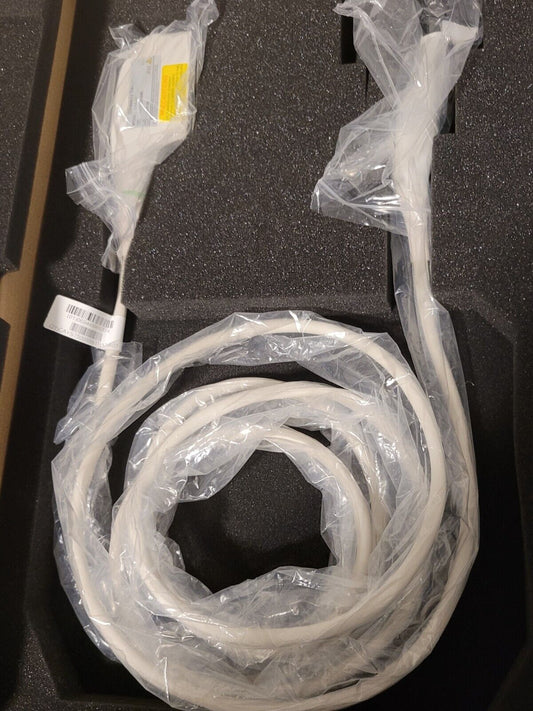

Mindray L14-5WU Linear Ultrasound Probe for Resona 7 (Demo Probe)

Regular price $999.00 USDRegular priceUnit price / per -